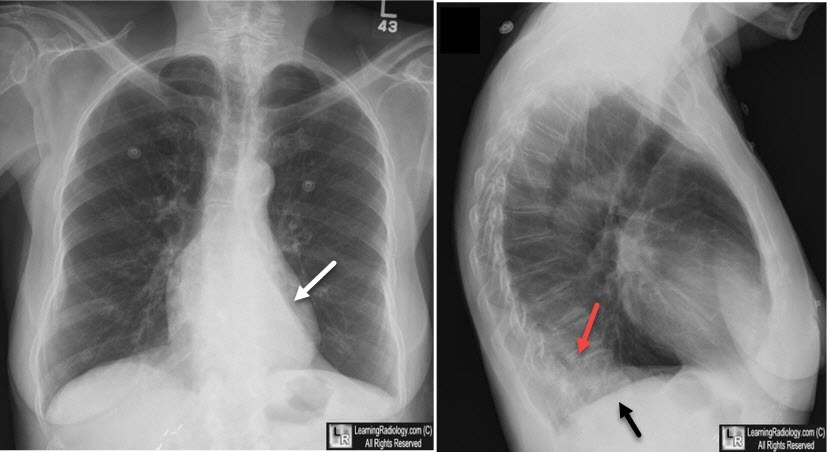

horseshoe lung associated with

scimitar syndrome